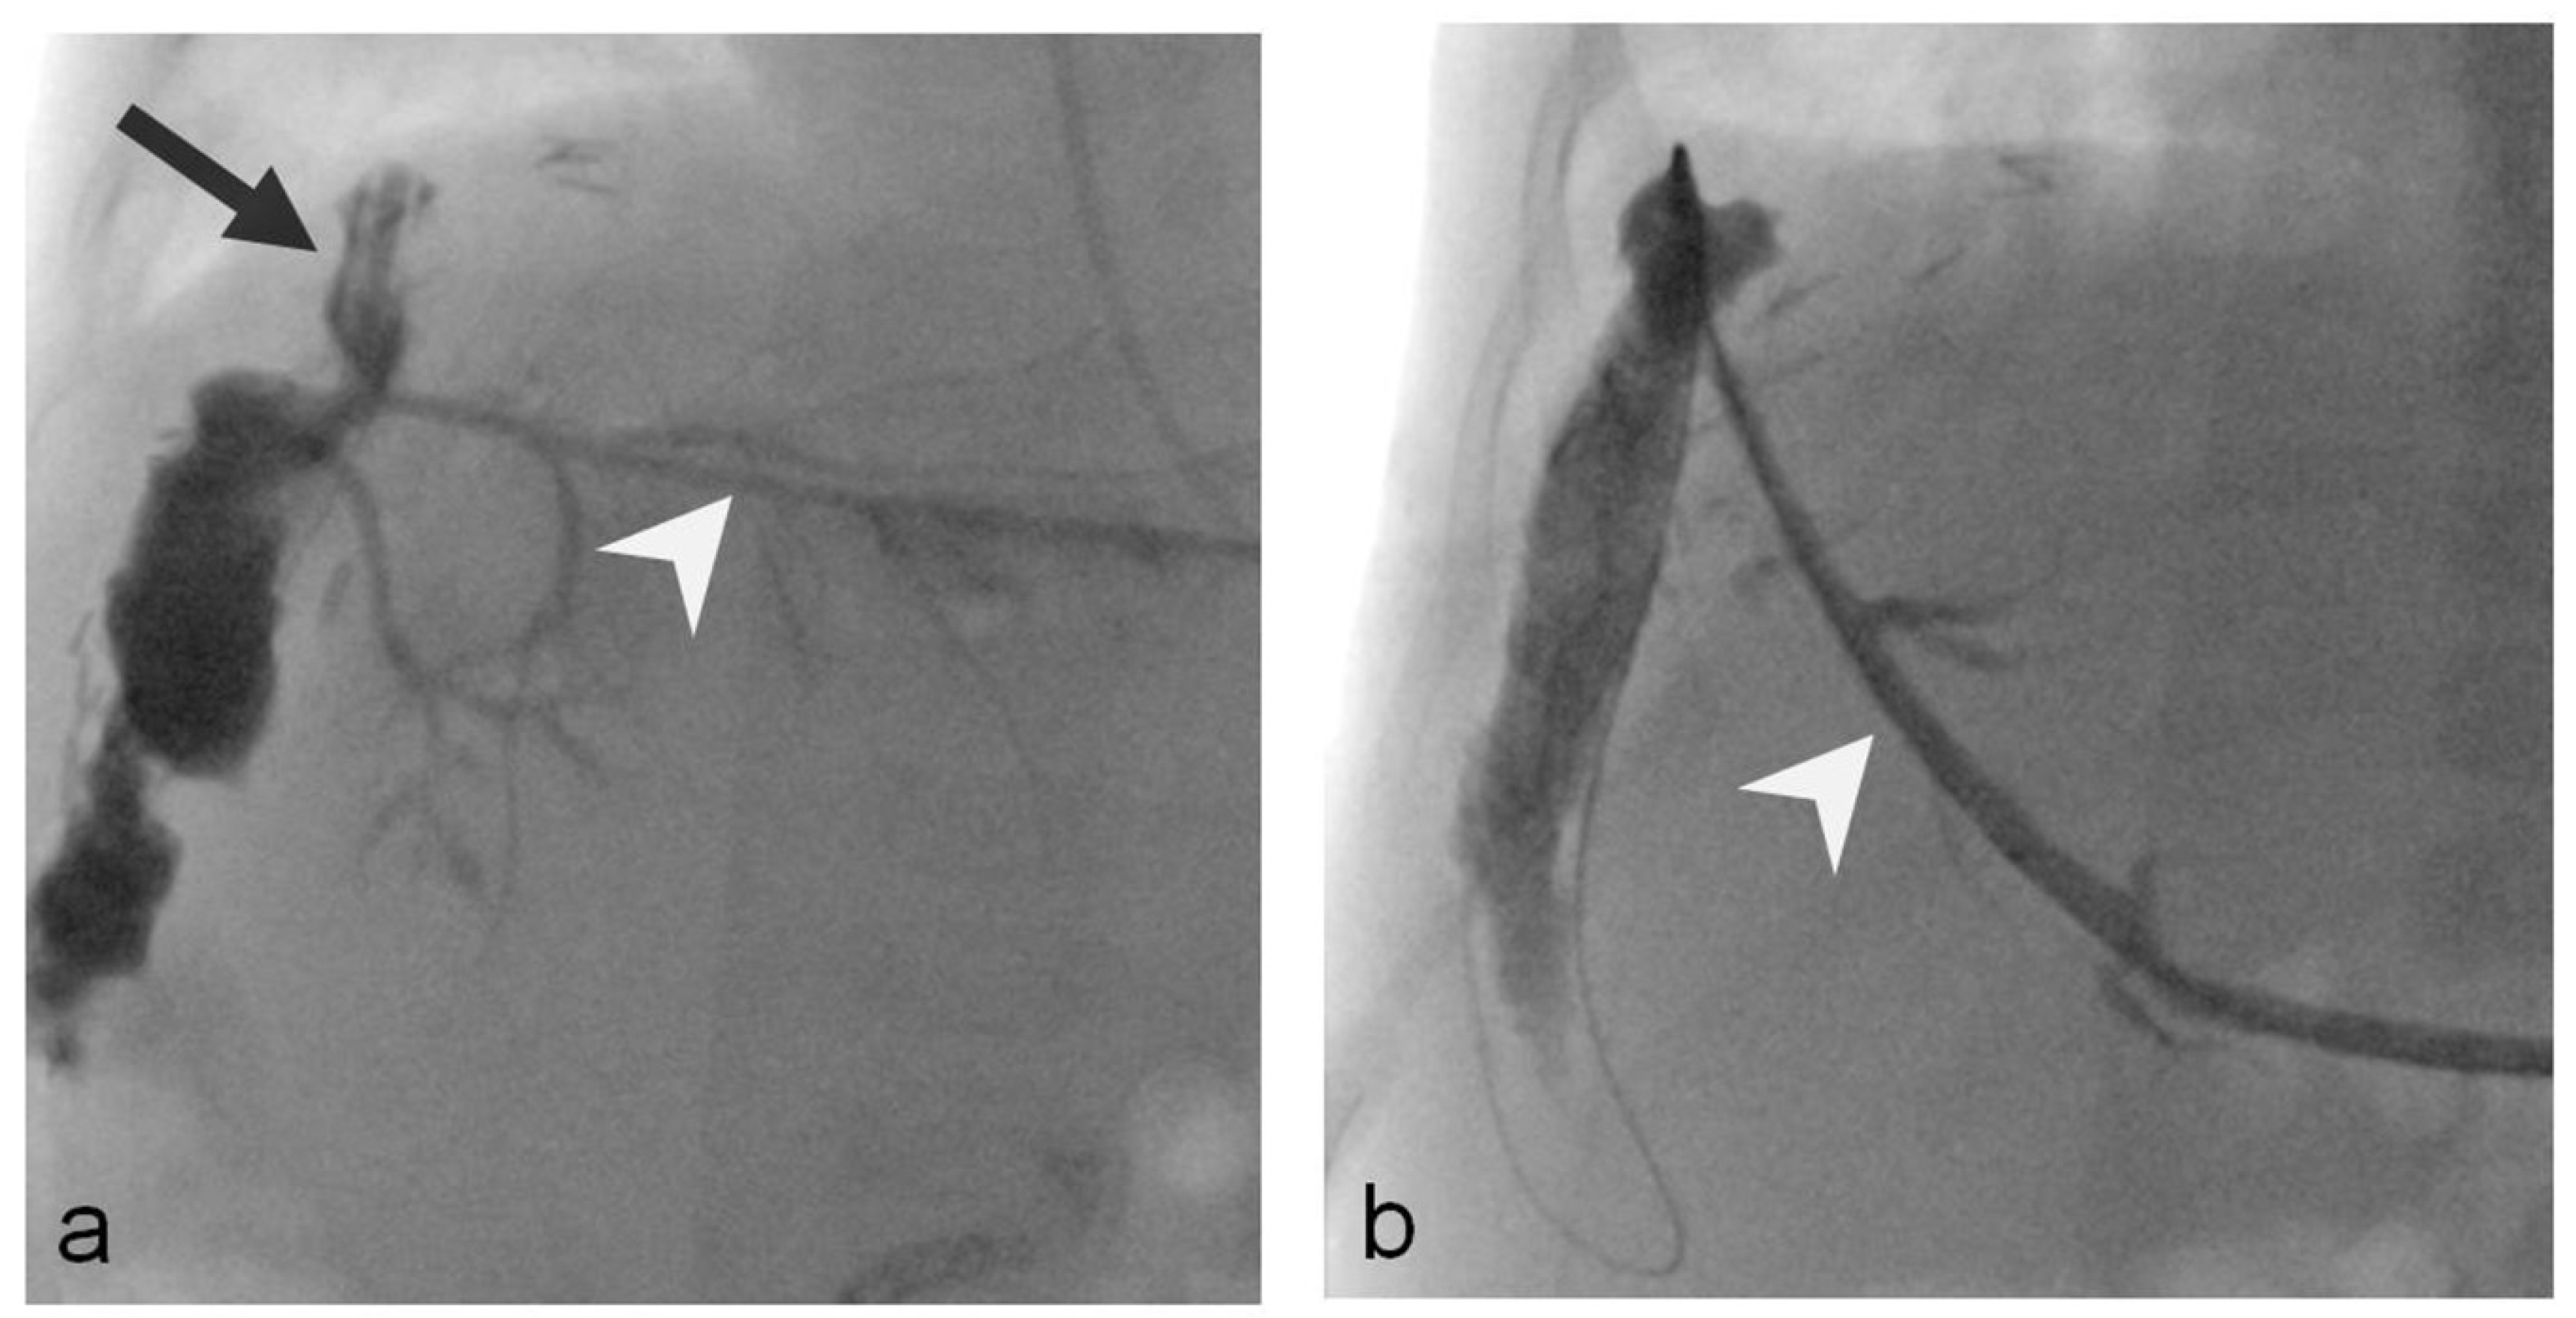

2.2. Procedure Technique

- Uller, W.; Wohlgemuth, W.A.; Hammer, S.; Knoppke, B.; Goessmann, H.; Loss, M.; Schlitt, H.J.; Stroszczynski, C.; Zorger, N.; Heiss, P. Percutaneous treatment of biliary complications in pediatric patients after liver transplantation. Rofo 2014, 186, 1127–1133. [Google Scholar] [CrossRef]